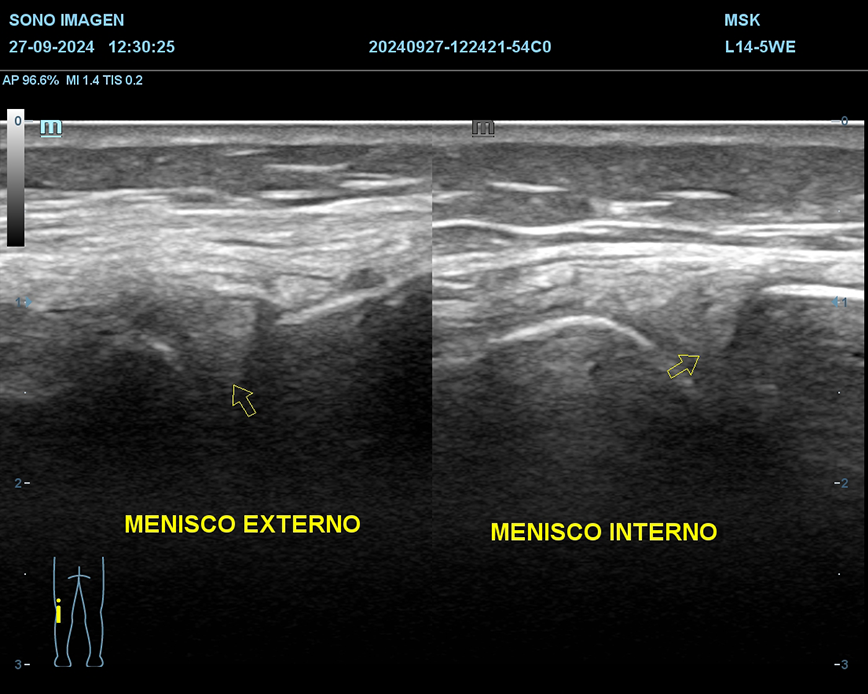

Ecografía de rodilla

- evaluación del dolor de rodilla

- lesiones de tejidos blandos: tendinosis, desgarros ligamentosos, rupturas meniscales.

- derrame articular

- inflamación o infección

- evaluación de lesiones deportivas

- quiste de Baker

- seguimiento postoperatorio

- traumatismos